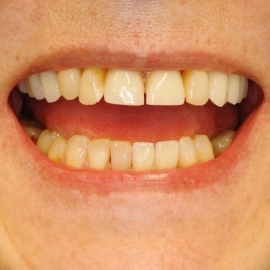

Bezzębie całkowite górne. Początkowo wykonane na mieście mosty całoceramiczne wydawały sie sukcesem, ale po roku pojawiły sie obrzęki i krwawienie z dziąseł. Pacjentka zgłosiła się do leczenia. Usunięto wszystkie zęby w szczęce. Sterowana regeneracja tkanek kości wyrostka, modelowanie kształtu i objętości tkanek miękkich, mosty porcelanowe przykręcane do implantów. Zadowalający wynik anatomiczny i estetyczny.